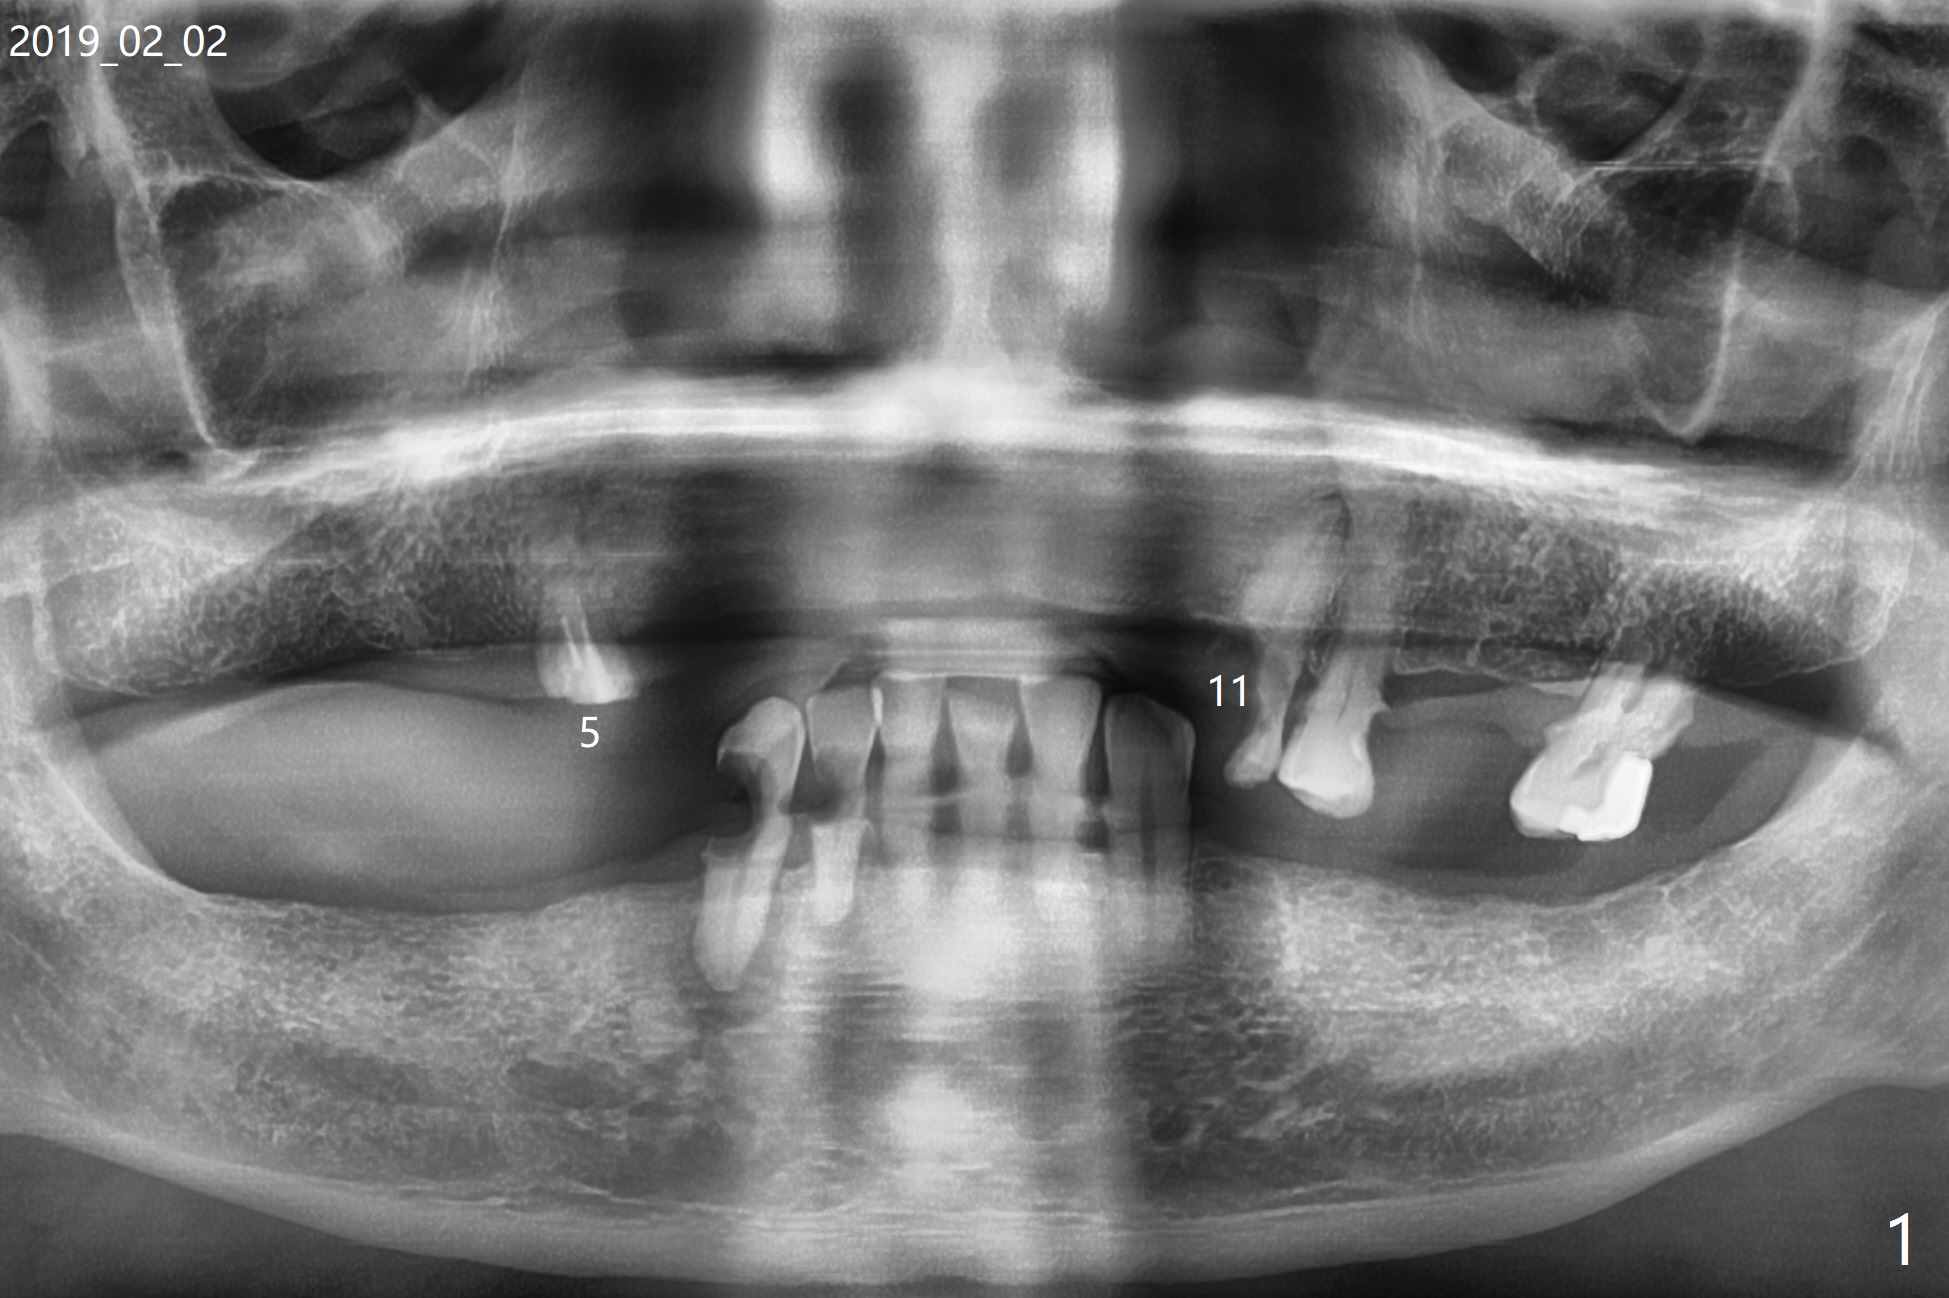

A 81-year-old man with upper and lower RPDs (Fig.1) requests extraction of the tooth #11 (Fig.2,3). After discussion, he agrees with socket preservation using Osteogen plug (Fig.4 O). The density at #11 is in fact higher than the neighboring healed socket (#10). Due to failure to transfer the flap to cover the socket and poor oral hygiene, the wound does not heal as well as expected 13 days postop (Fig.5).